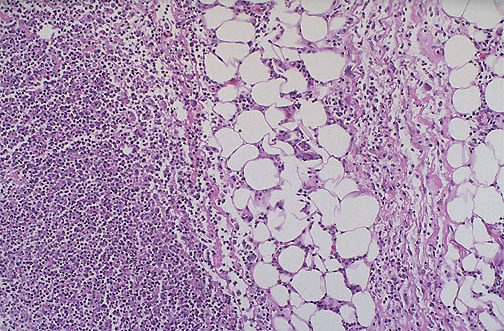

| Necrotizing fasciitis is most likely to occur with penetrating trauma and with conditions that cause ischemia to soft tissues from vascular occlusion, particulary diabetes mellitus, though vasculitis may also lead to this complication. Organisms such as Staphylococcus aureus and streptococcal species are typically cultured. |